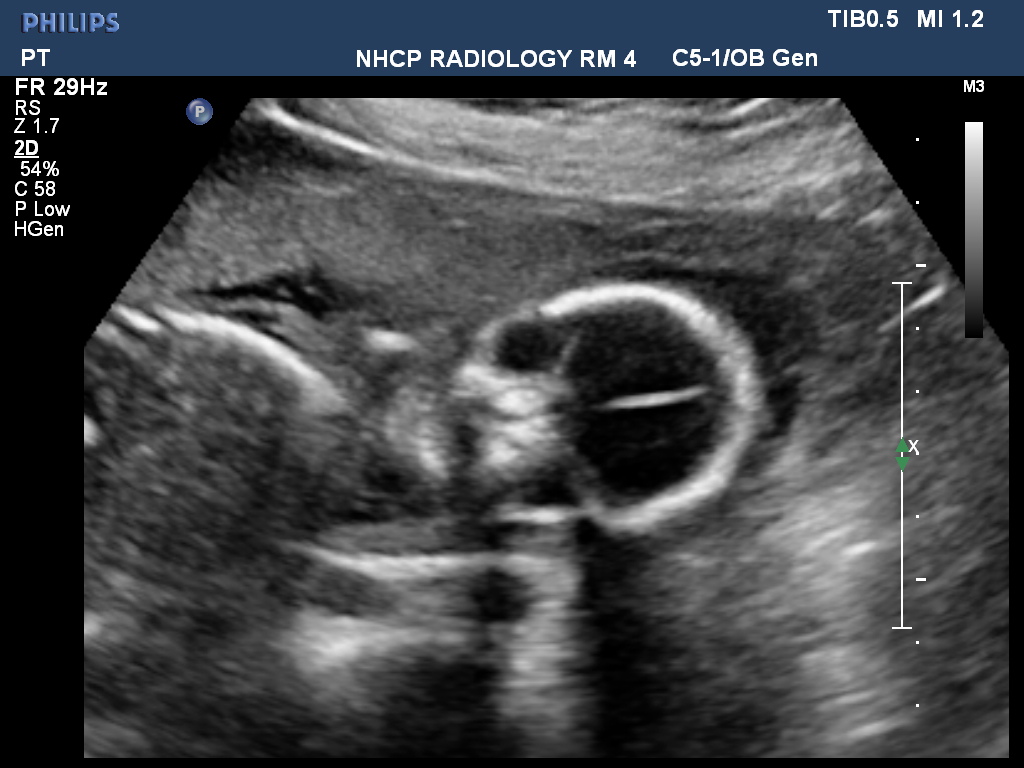

We weren't told much. But Hadley sure did keep those legs crossed tight. We got this CD with about 8 pictures. These were the best. :P We have another scan because the technician couldn't get a good read on her heart, or something... It was beating just fine(: No worries. But now we may get another try at the potty shot. Although, I just know I have a little girl inside my tummy right now. <3

| Look at that little hand at the end of the arm!! On the left! <3 |